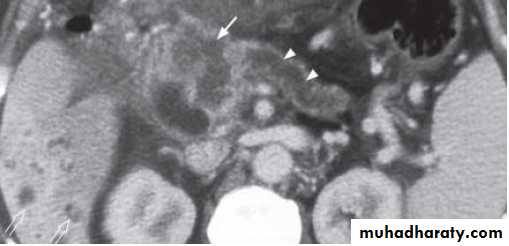

Contrast enhanced axial computed tomography (CT) showing a large necrotic tumour in the pancreatic head (arrow). The pancreatic duct is dilated (arrowheads). Note the presence of multiple small irregular hypodense lesions in right lobe of liver (open arrows) representing liver metastasis.